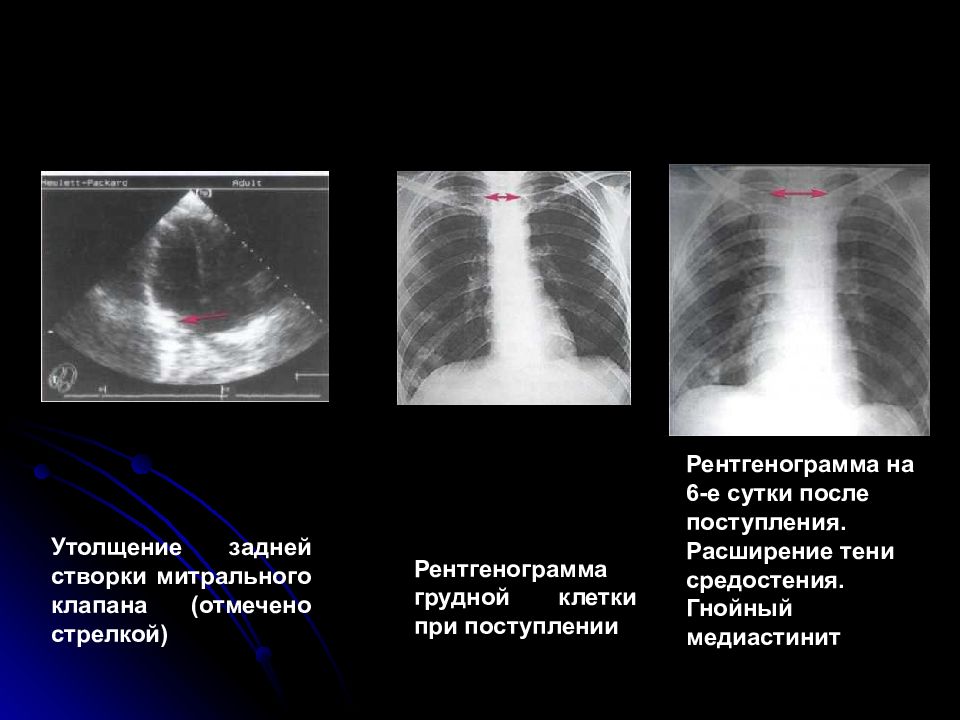

Медиастинит осложнения

Медиастинит осложнения 134 фото